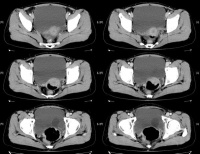

影像学检查可明确诊断。B型超声检查可显示膀胱内有薄壁囊性肿块。静脉尿路造影典型者表现为输尿管末端“蛇头”状膨大,伴或不伴肾输尿管扩张积水,合并重复畸形时亦可显示。膀胱镜检可见输尿管开口处呈囊状扩张,开口呈针尖样随输尿管蠕动时张时缩。